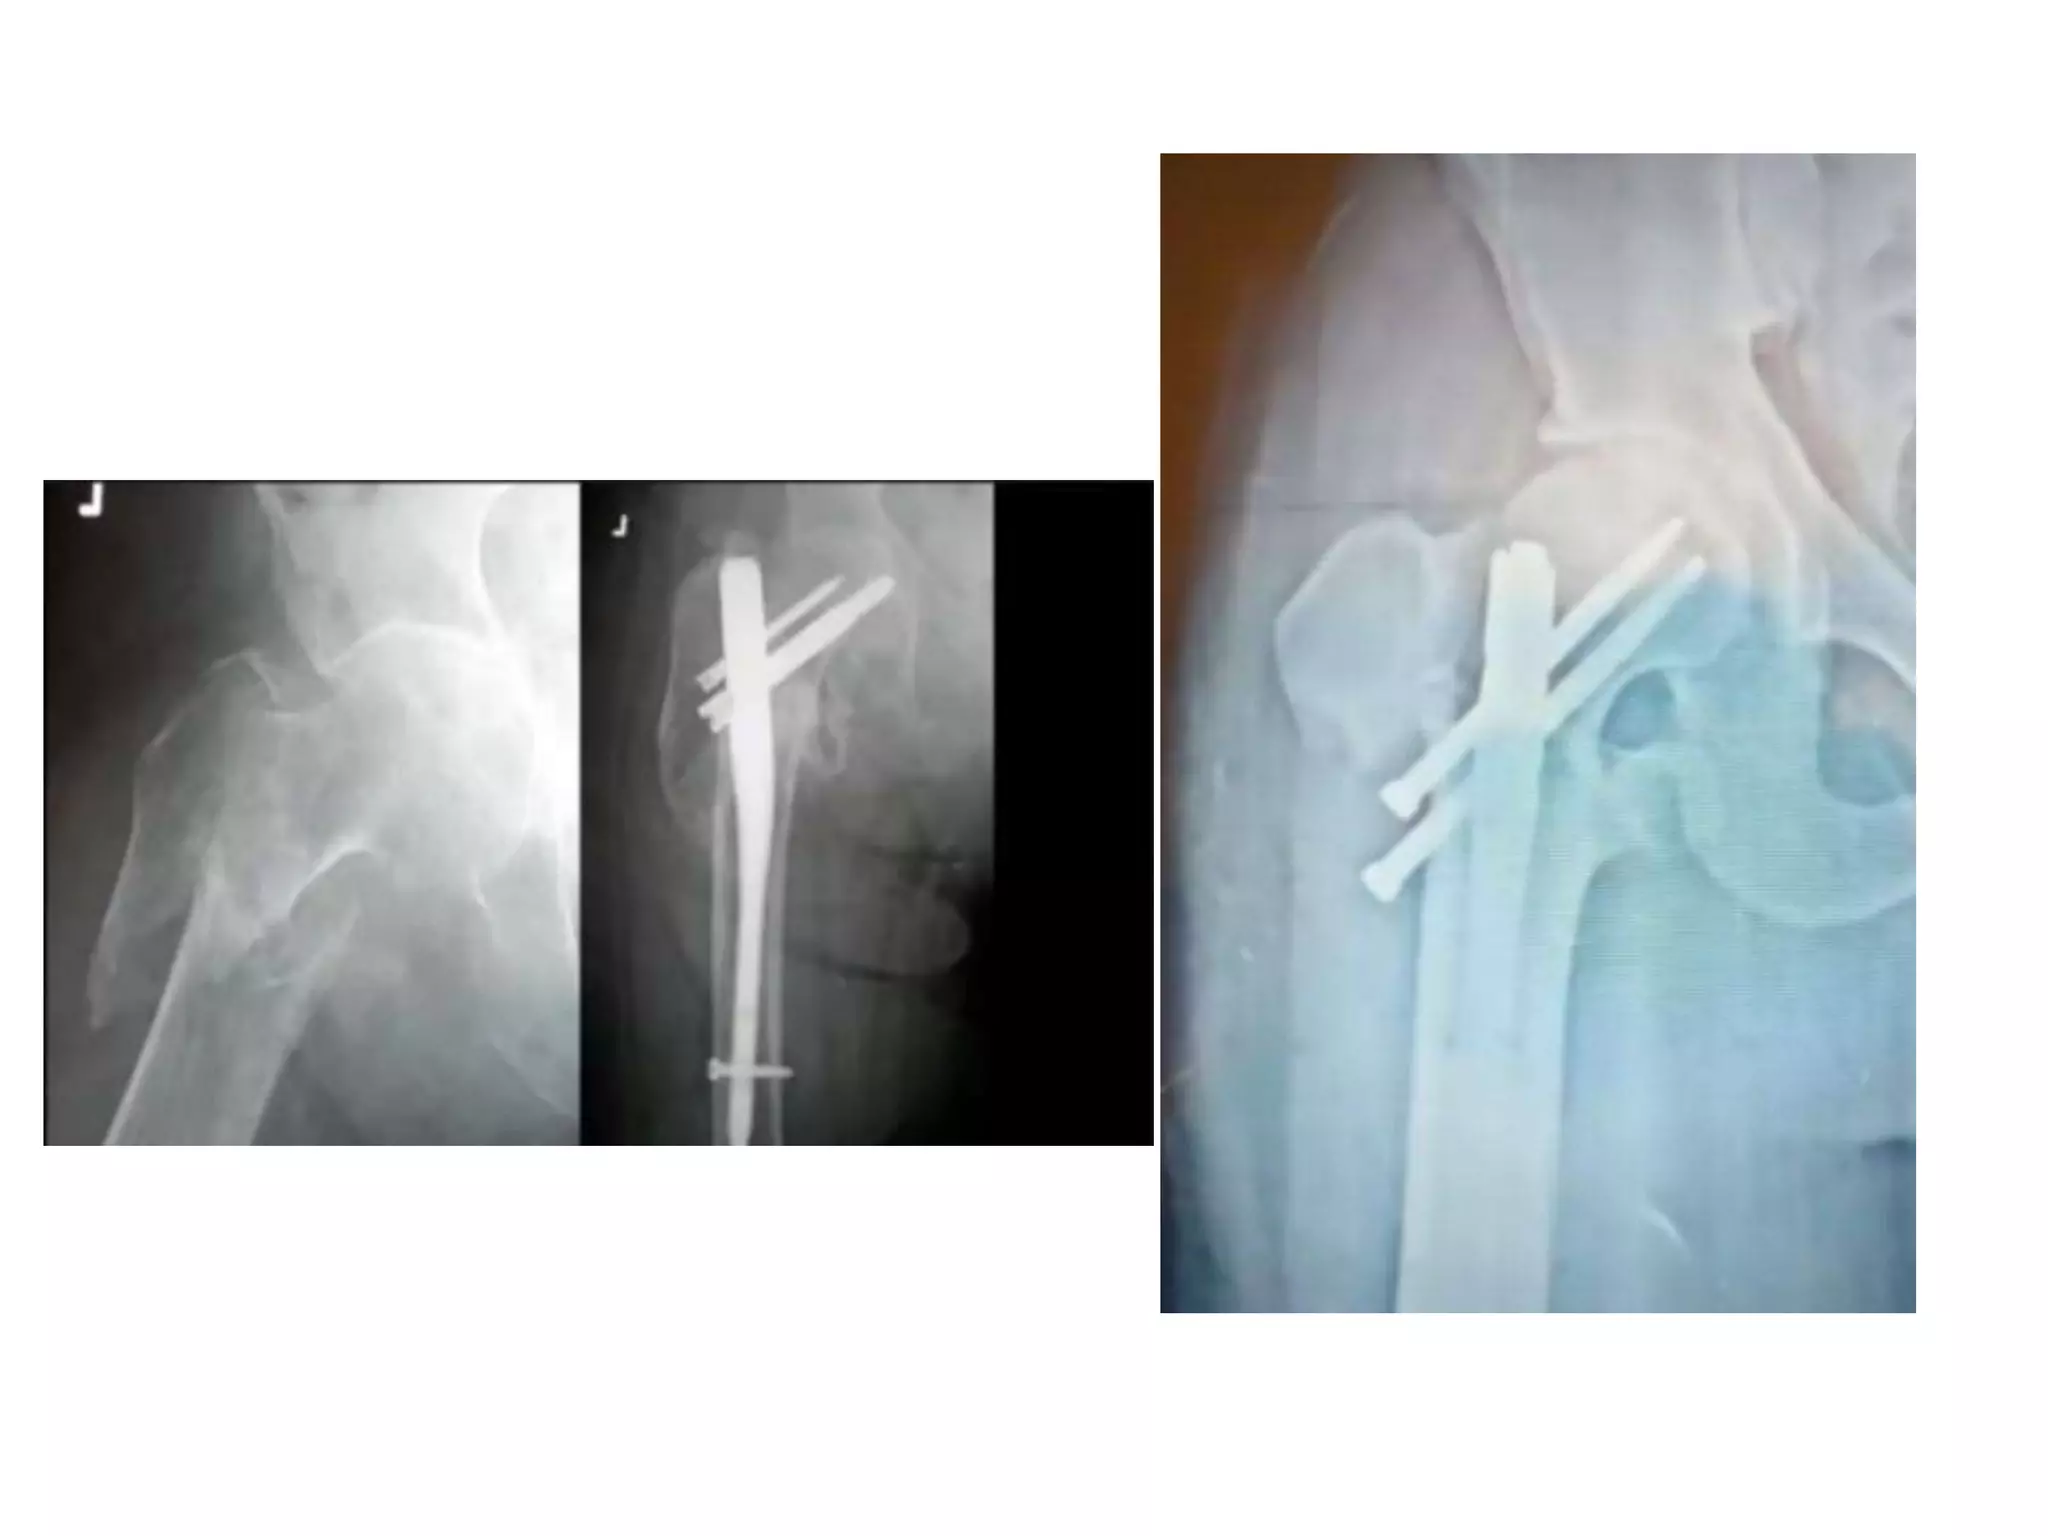

Case

50Year old male .H/O RTA. Otherwise fit.

Case 50Year old male.H/O RTA. Otherwise fit.